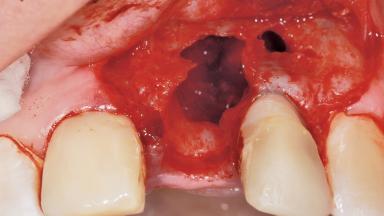

Late Placement of an Implant in a Maxillary Left Central Incisor Site

A 36-year-old female patient was referred for the replacement of the upper left central incisor (tooth 21), which had fractured. Although the tooth had been asymptomatic for many years, the crown began to loosen, at which time she presented to her dentist for an assessment. Teeth 21 and 22 had both been endodontically treated many years previously. She was a healthy individual and a non-smoker.

Soft Tissue Grafting Simultaneous

Soft Tissue Anatomy Intact Defective